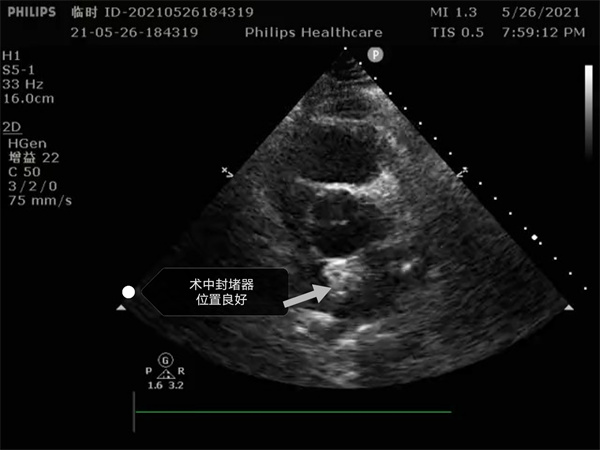

尤其是患者是個三房心,正常的人是有二個心房,這是一種少見的先天性心臟畸形, 如何在三房心把這個洞堵住,而且不影響心臟正常結(jié)構(gòu),是這個手術(shù)難點。沈主任組織全科進行術(shù)前討論,5月26日下午5點開始手術(shù),導絲如何在不規(guī)則的只有米粒大小的卵圓孔里通過,鞘管如何通過,如何進入卵圓孔連接的副房,避免封堵器夾住隔膜,這些難點在術(shù)中被沈主任團隊一一化解,手術(shù)歷時二小時,隨著封堵器成功釋放,導管室外響起來熱烈的掌聲。

就這樣三房心合并卵圓孔未閉發(fā)生過三次腦梗的患者,在安康市中心醫(yī)院心內(nèi)科導管室成功進行了國內(nèi)第二例介入封堵手術(shù)。